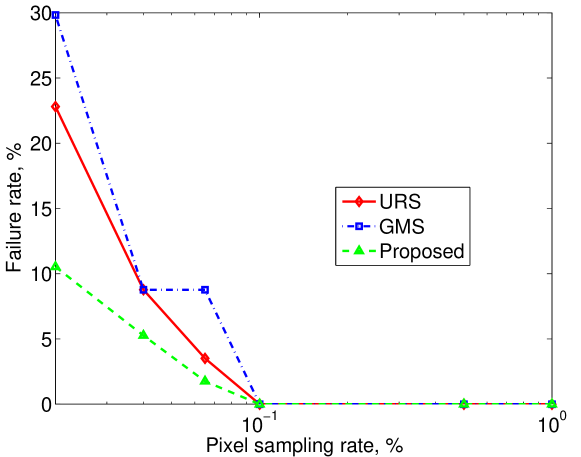

Figure 2 shows registration failure rate for the following set of pixel sampling rates (in %): . We define a failure as any case with error exceeding 10mm in any of the VOIs. We can see that the proposed approach consistently outperforms other approaches in terms of robustness.

Such results support our conjecture that balancing image exploration induced by URS and the exploitation of the prominent image features induced by GMS using a small problem specific training dataset can significantly improve and accelerate the performance of the registration algorithm. Overall, the proposed technique at 0.1% pixel sampling rate is better than other techniques at 1% pixel sampling rate, simultaneously maintaining zero failure rate and mm accuracy. Thus on average our approach can use 10 times less pixels for registration, achieve 0 failure rate and improve accuracy over the other two techniques. This is significant improvement over both alternative methods and it allows to reduce the time from 210 seconds per registration for pixel sampling rate to 32 seconds per registration for pixel sampling rate in our implementation.